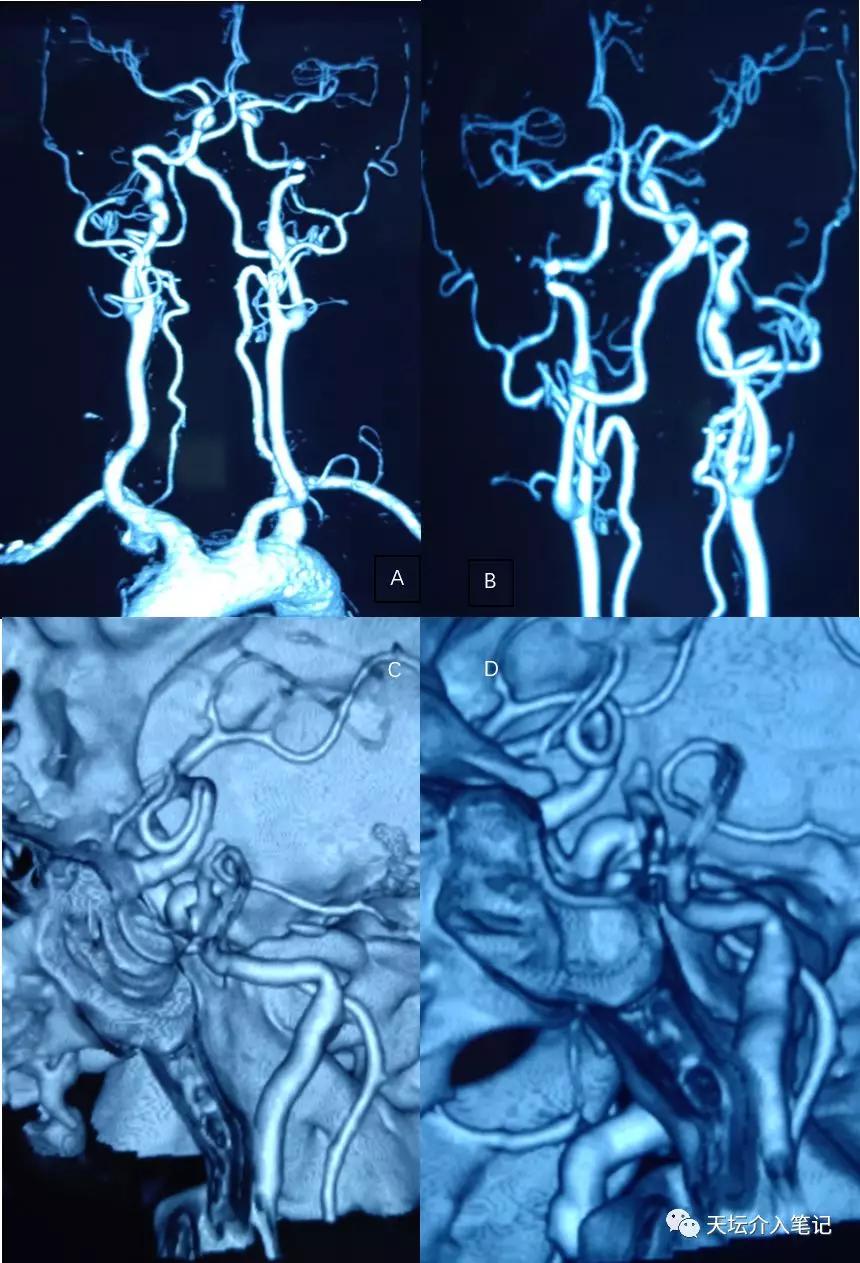

图 1

A,B 患者院外MRA; C,D院外MRA显示椎动脉瘤样扩张